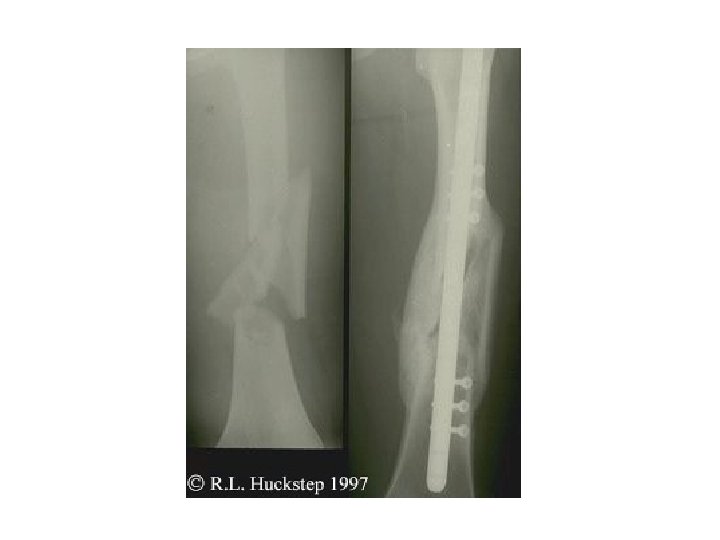

Fractures • Simple ; spiral, oblique and transverse • Complex – Complete separation of bone; major blow, intraarticular , comminution and segmental • Open vs close

Segmental fx